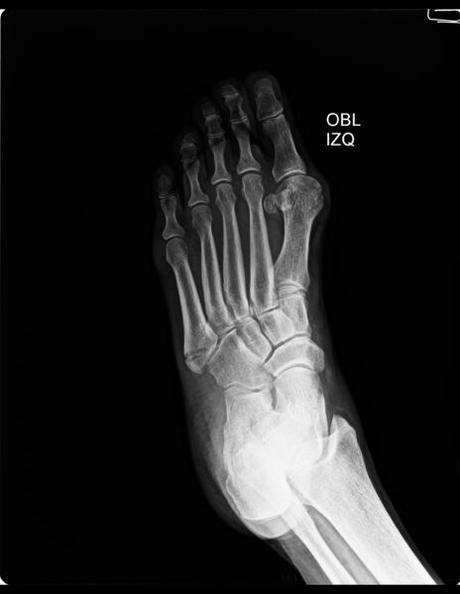

Se realiza proyección DORSOPLANTAR Y OBLICUA DE PIE IZQUIERDO

Densidad mineral ósea preservada.

Huesos del tarso y falanges conservan su morfología, sin lesiones.

No se observan lesiones líticas o blásticas.

Espacios articulares de amplitud normal.

Relaciones articulares conservadas.

Plano de tejidos blandos sin densidades patológicas.